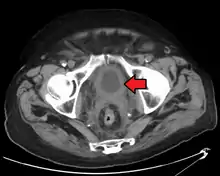

The most common sites for bladder cancer metastases are the lymph nodes, bones, lung, liver, and peritoneum.[76] The most common sentinel lymph nodes draining bladder cancer are obturator and internal iliac lymph nodes. The location of lymphatic spread depends on the location of the tumors. Tumors on the superolateral bladder wall spread to external iliac lymph nodes. Tumors on the neck, anterior wall and fundus spread commonly to the internal iliac lymph nodes.[77] From the regional lymph nodes (i.e. obturator, internal and external lymph nodes) the cancer spreads to distant sites like the common iliac lymph nodes and paraaortic lymph nodes.[78] Skipped lymph node lesions are not seen in bladder cancer.[77]